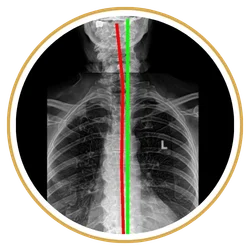

Chiropractors take x-rays to see the internal condition of the spine. X-rays also reveal if there are any underlying spinal disorders, such as arthritis of the spine, abnormal development, disc disorders, bone spurs, and spinal deterioration.

Having an x-ray taken before any adjustment helps chiropractors make a correct diagnosis. Combining x-rays with other exams will benefit the patient ultimately.